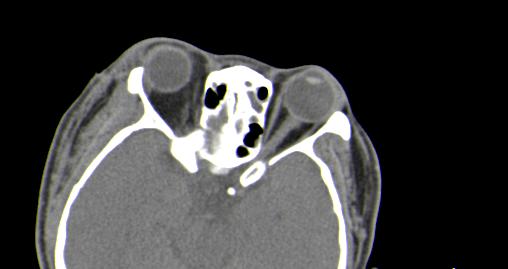

以下是引用皎皎白驹在2006-11-29 8:48:00的发言:[br]影像表现:双侧筛窦和上颌窦、鼻腔内均密度增高,右侧视神经增粗、弯曲,左筛窦顶部筛板及右侧纸板近视神经孔区可见骨折线。[br]结合临床表现考虑:右侧筛窦纸板近视神经孔区骨折致右侧视神经损伤。最好做个眼眶冠状扫描,更明确右侧视神经管是否狭窄。

以下是引用w_jianhua在2006-11-29 10:07:00的发言:[br]影像表现:双侧筛窦和上颌窦、鼻腔内均密度增高,右侧视神经增粗、弯曲,左筛窦顶部筛板及右侧纸板近视神经孔区可见骨折线。[br]结合临床表现考虑:右侧筛窦纸板近视神经孔区骨折致右侧视神经损伤。最好做个眼眶冠状扫描,更明确右侧视神经管是否狭窄。 [br] [br]支持[br]

以下是引用守望可可西里在2006-11-29 9:46:00的发言:[br][quote]以下是引用皎皎白驹在2006-11-29 8:48:00的发言:[br]影像表现:双侧筛窦和上颌窦、鼻腔内均密度增高,右侧视神经增粗、弯曲,左筛窦顶部筛板及右侧纸板近视神经孔区可见骨折线。[br]结合临床表现考虑:右侧筛窦纸板近视神经孔区骨折致右侧视神经损伤。最好做个眼眶冠状扫描,更明确右侧视神经管是否狭窄。